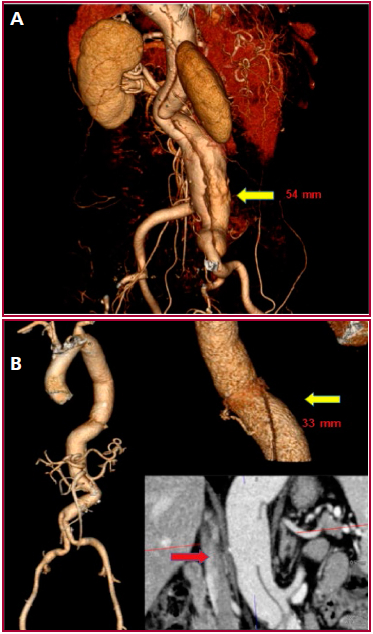

En mayo de 2013 se constató la progresión del aneurisma de aorta abdominal que medía 54 mm de diámetro. (Figura 3A). Dada la configuración del flap de disección y el compromiso de ambas luces de los vasos viscerales, tampoco fue posible el tratamiento endovascular. Se decidió conservar el segmento aórtico intermedio entre el tronco celíaco y ambas arterias renales (de 39 mm de diámetro). Se abordó por una laparotomía xifopubiana, con clampeo en el segmento intermedio infrarrenal, y se realizó el reemplazo aorto biíliaco infrarrenal, con prótesis de Dacron 18 × 9 mm. La paciente cursó un posoperatorio sin complicaciones y se le dio el alta a los 6 días. Al año, la paciente se encontraba asintomática, se detectó por angio-TC vasos supraaórticos viscerales y bypass aorto biíliaco permeables, además de la aorta descendente residual sin dilatación y con flap de disección sin compromiso visceral (Figura 3B).